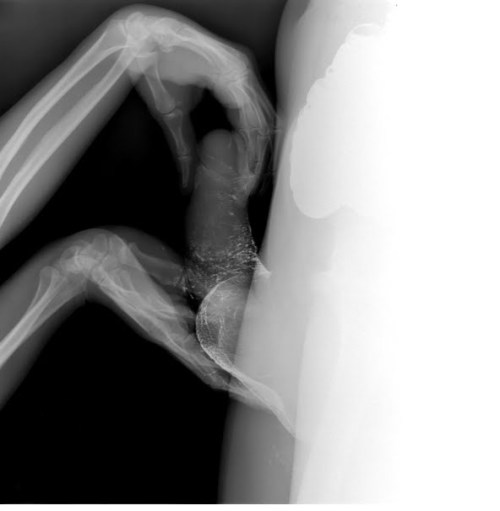

[…] Cuando el artista belga Wim Delvoye realiza imágenes por rayos X de un beso o de actos sexuales, imágenes X por medio de rayos X, no hace otra cosa que apropiarse estéticamente de técnicas científicas a veces de punta, reintroduce la «skiagrafía», excluida antiguamente por la filosofía, y, en la ciencia, lo concerniente al acto sexual, que ella excluye.

Podríamos evocar dos imágenes radiográficas de Wim Delvoye. Estas imágenes tomadas por rayos X, clasificables en la góndola de las imágenes X, poseen una fuerza de verdad extrema. Sin embargo, no donde uno cree, no donde uno ve. Al mostrar un beso o una felación, son para verlas, desde luego, como toda imagen, pero ellas muestran lo que no se ve a simple vista, el interior de los cuerpos en actividad. Ellas nos sitúan en un tiempo posterior al cine pornográfico. El valor del surgimiento del cine pornográfico, si ese valor existe, es en el fondo, haber mostrado algo, una parte de la anatomía que el cine jamás había mostrado, los órganos sexuales en actividad. Las imágenes de rayos X, al ir más allá de la anatomía, van más lejos: van al sexo bajo la piel. Por otra parte, si bien tales imágenes cumplen el sueño de la cámara pornográfica de mostrar desde lo más cerca posible, esto no produce exactamente una mayor excitación sexual. En verdad, las imágenes de Wim Delvoye tienden a mostrar una cosa que no se había visto nunca: cómo funciona el sexo. Sin embargo, debería decirse más bien que lo que estas imágenes muestran, es que no se lo ve. Más aún, que lo normal es que no se lo vea.

[…] Para más exactitud, yo diría que estas imágenes de rayos X, que es posible reunir con el dibujo anatómico de Leonardo en el que se representa el corte de un coito muestran sobre todo que hay algo que no se puede ver: cómo funciona el amor, cuál sería el secreto del sexo. Tal es su dimensión crítica. Ellas se dirigen también a los médicos y a todos para decir que la búsqueda de la transparencia del cuerpo es una fantasía, porque hay algo que jamás se podrá ver ni saber, y por lo tanto dominar: la relación sexual. Pueden ustedes radiografiar el cuerpo, autopsiar el cuerpo, volverlo todo lo transparente que quieran, pero jamás verán con sus ojos el secreto de la relación sexual; o mejor dicho, jamás verán la única verdad que hace saltar los ojos: que no hay nada que ver, que no hay secreto. Esto es lo que, al fin de cuentas, resiste definitivamente a la voluntad del amo de que «eso funcione».